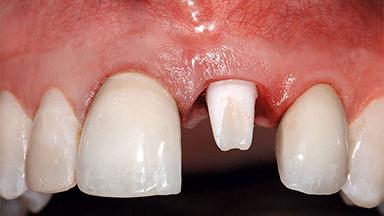

Replacement of a Missing Upper Left Central Incisor: Late Placement of an RC Bone Level Implant, CAD/CAM Zirconia Abutment

A healthy 37-year-old female patient was referred for a consultation on the replacement of missing tooth 21 with an implant-supported restoration. She stated that several years previously the tooth had been traumatically avulsed following a motor vehicle accident. The tooth was replaced with a three-unit fixed partial denture (FPD) immediately afterwards. Over time, she became disillusioned with the FPD and looked for a different option, including orthodontic therapy. She presented still in her orthodontic appliances, with the pontic sectioned free from the FPD but attached to the archwire. Her orthodontist felt that orthodontic treatment had been successfully completed, but nevertheless referred her before removing the appliances in case adjustments were necessary.